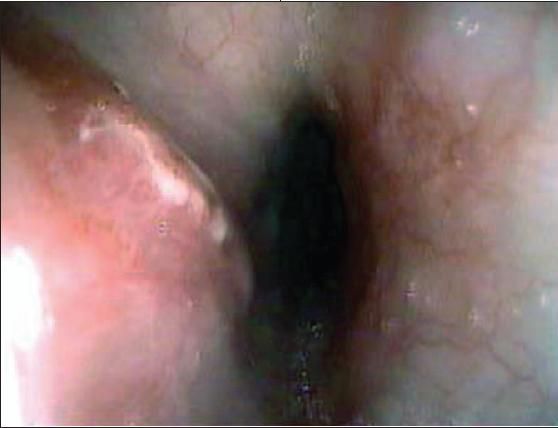

Fluids and lansoprazole were started intravenously.The patient's esophagram and upper endoscopy findings are shown

Case 2: The endoscopic findings showed a large area (3 5 cm) of ulceration, edema, and inflammation in the lower esophagus.